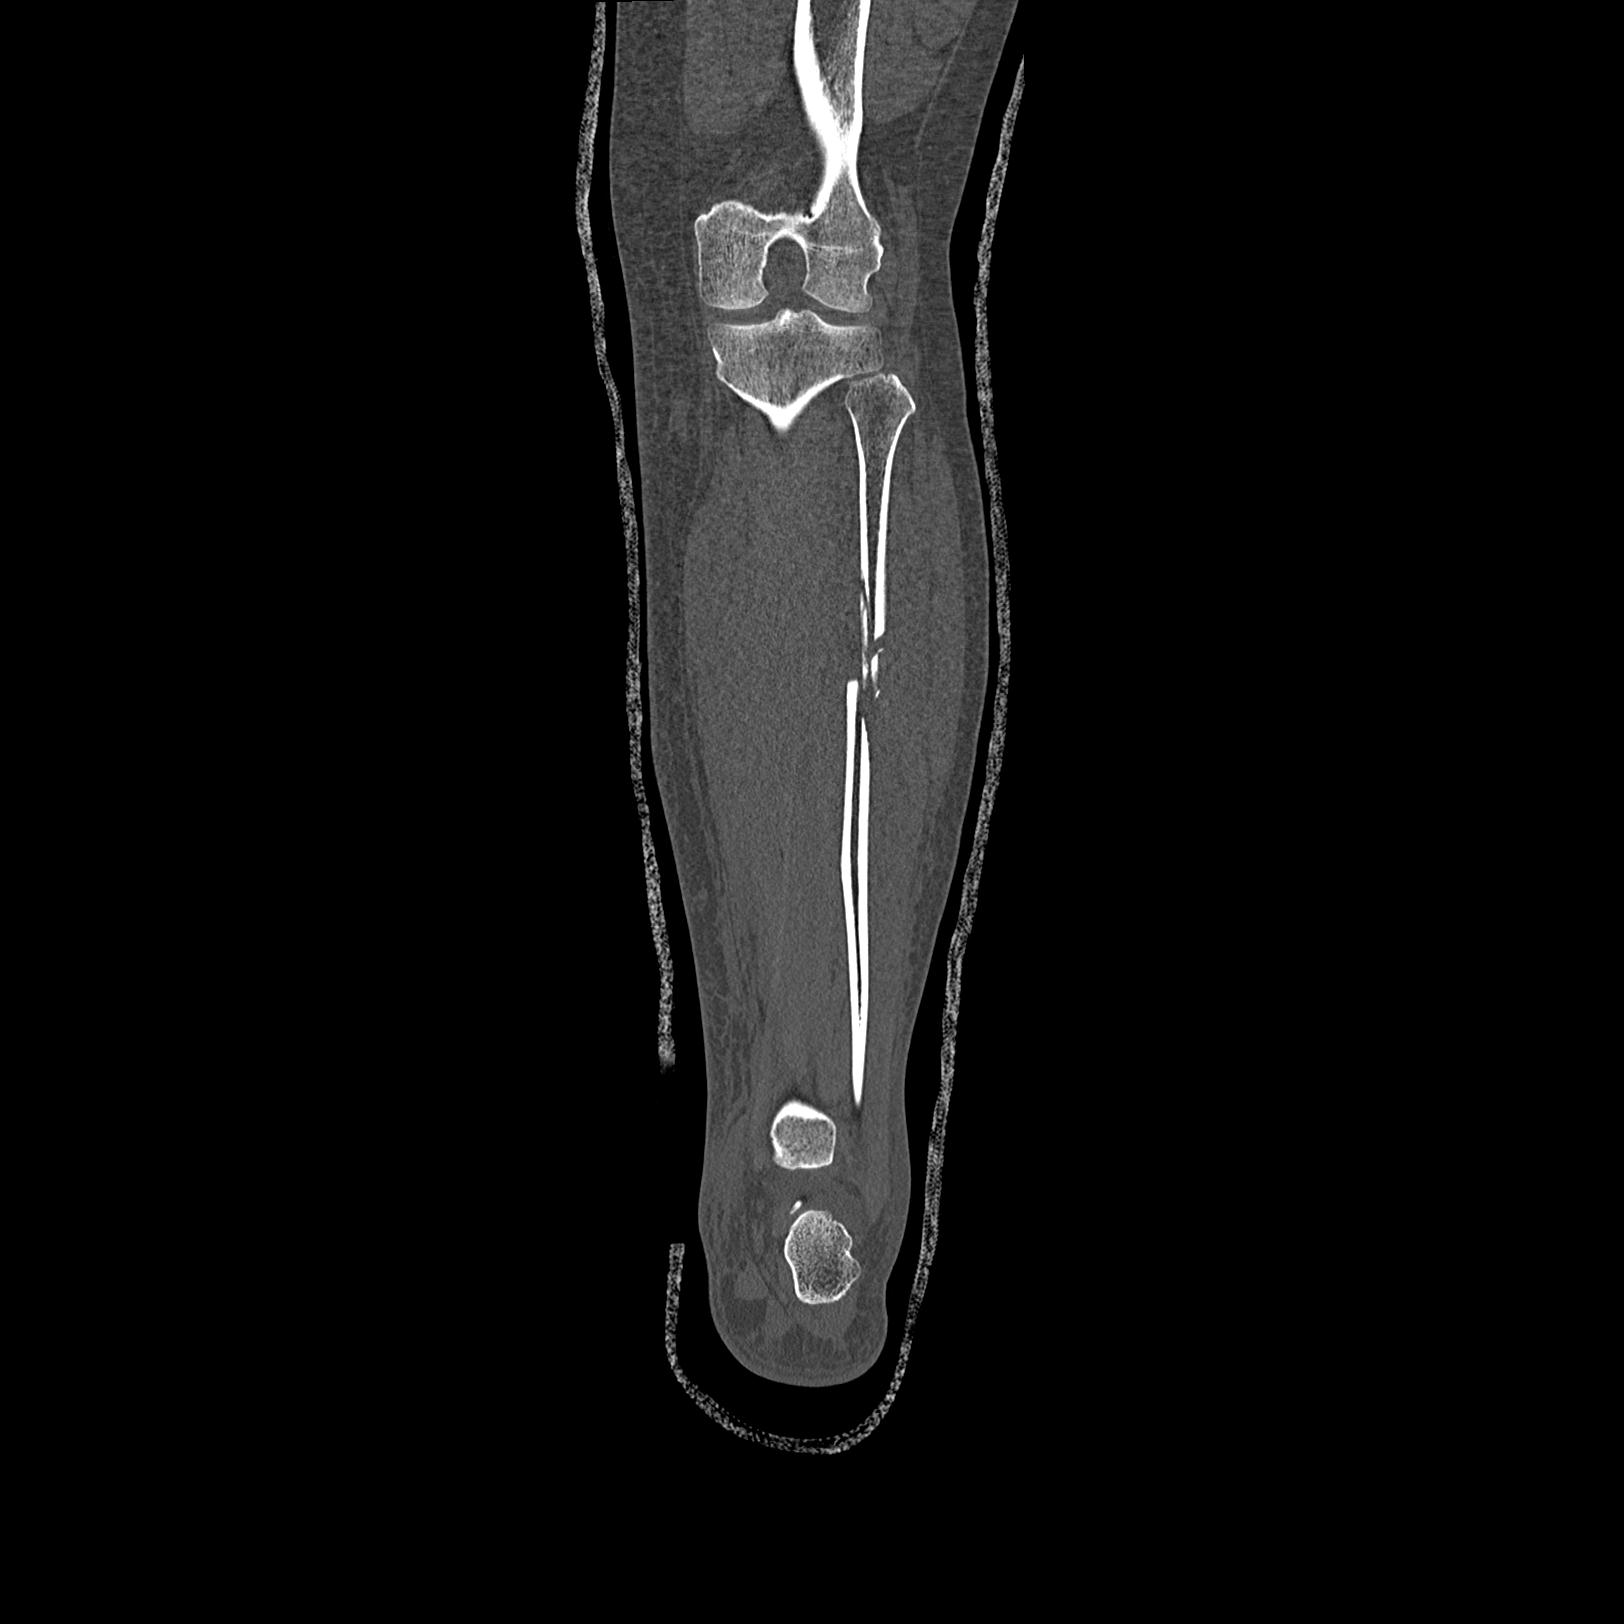

102803 1/12(キウスなし) 1/27 左下腿 4R 30歳女性 左脛骨軸内釘